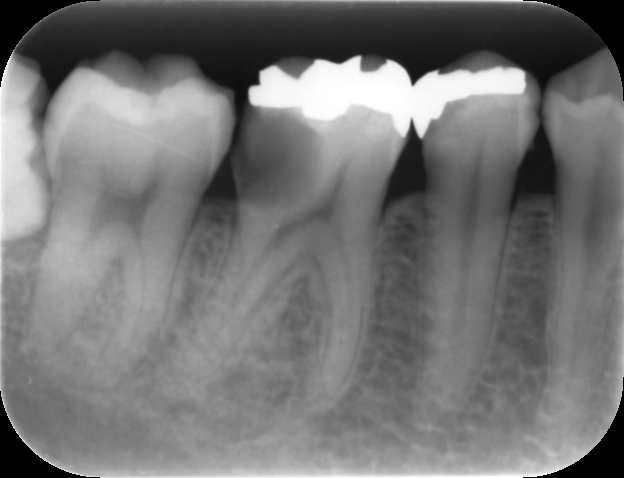

定期検診時、治療した部分に問題が無いかを確認します。必要に応じてレントゲンやCT撮影を行い、根管治療の予後確認を行います。

また、歯髄を失った歯は歯根破折を起こしやすいため、噛み合わせに問題が無いかも確認します。

抜髄根管治療6か月後のレントゲン画像です。

根尖部に病変は認めず、根管治療の予後に問題はありません。

オールセラミッククラウンの適合状態も非常に良好です。